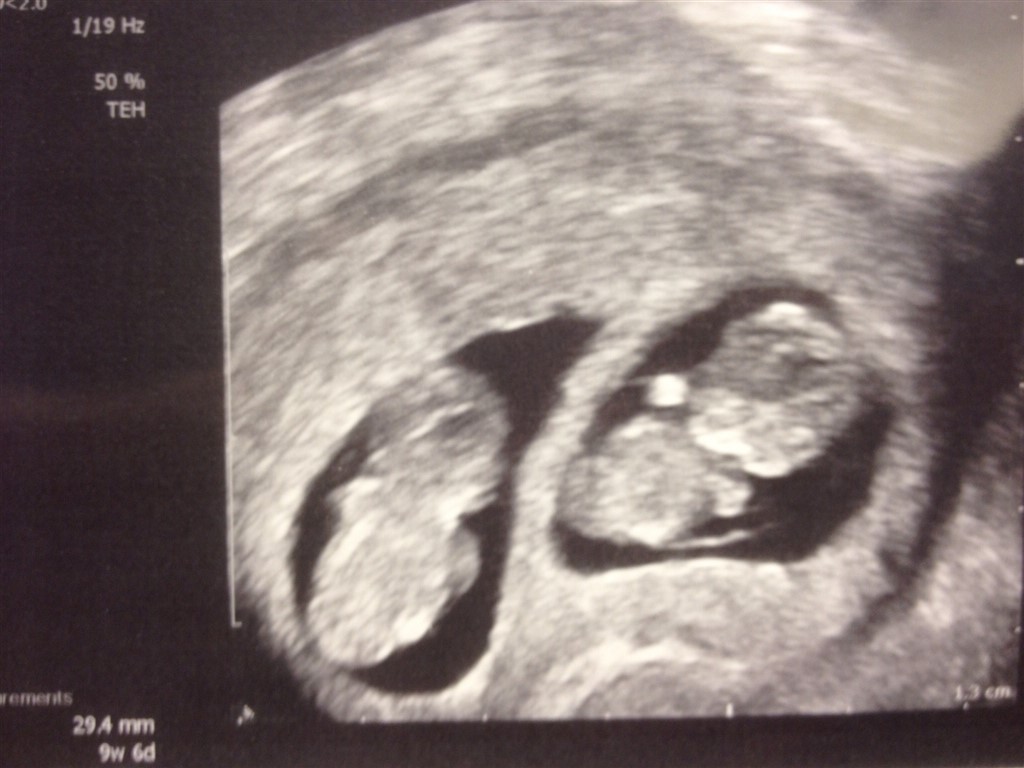

Du kan se små babyer hvis der er to.. Det her er fra 9+6 af vores drenge..

Vedhæftede fotos (klik for at se i fuld størrelse)